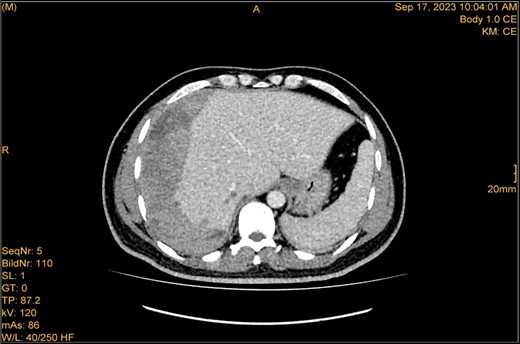

A 41-year-old male with a clear medical background, presented to the Emergency Department with right upper quadrant (RUQ) abdominal pain for two days, associated with fatty dyspepsia, anorexia, nausea, and vomiting. On arrival, his heart rate was 111 bpm with a blood pressure of 128/94 mmHg. On examination, a yellowish discoloration of skin and sclera was noted with a negative murphy sign. Investigations showed elevated liver enzymes (LFT). An initial abdominal ultrasound showed a distended gallbladder with a thickened wall and multiple stones, largest measuring approximately 1.4 cm, and a common bile duct measuring 5 mm (Fig. 1). A magnetic resonance cholangiopancreatography (MRCP) identified a tiny 4-mm mid-cystic duct stone without intrahepatic biliary dilatation. After the initial management, an emergency LC was performed, which posed minimal challenges. Fortunately, no intraoperative complications were reported. A drain was kept in the subhepatic area, and the patient was kept under close observation. Second day postoperatively, the patient experienced dizziness and an intense RUQ pain despite proper analgesia. His heart rate was 89 bpm with a blood pressure of 107/64 mmHg. Investigations showed a drop in hemoglobin level from 13.8 to 9.9 g/dl. An abdominal ultrasound showed a right subcapsular heterogeneous collection with a scalloped liver surface (Fig. 2). Therefore, an initial diagnosis of ISH post-LC was considered. Following the initial fluid resuscitation and blood transfusion, a further decline in hemoglobin level was noted reaching 8.8 g/dl. Further blood transfusion was commenced achieving stabilization. Further CT scan showed subcapsular hepatic hematoma measuring 7.1 × 19 × 21 cm, in its transverse, anteroposterior, and craniocaudal diameters, respectively, with no evidence of active extravasation (Fig. 3) confirming the final diagnosis of ISH post-LC. A multidisciplinary decision was made to continue conservative management after a proper explanation of the potential risk of sudden rupture of hematoma. The patient’s clinical condition and hemoglobin level, in addition to drain output, were meticulously monitored in the general ward, ensuring early detection of deterioration. Four days later, a follow-up CT scan revealed no new significant interval changes (Fig. 4). Nine days postoperatively, the patient was discharged with a follow-up appointment, which showed almost complete resolution.

Enhanced CT scan utilizing bleeding protocol. Status post-LC identified significant ISH with internal hyperdensity measuring 7.1 × 19 × 21 cm, in its transverse, anteroposterior, and craniocaudal diameters, respectively. Adjacent hyperemic liver parenchyma with intraparenchymal hematoma noted at segment 5, measured 4.7 × 4 × 4.7 cm. Intraparenchymal hypodensities noted at segments 8 and 4b, likely represent hepatic contusions and lacerations. No evidence of active contrast extravasation.